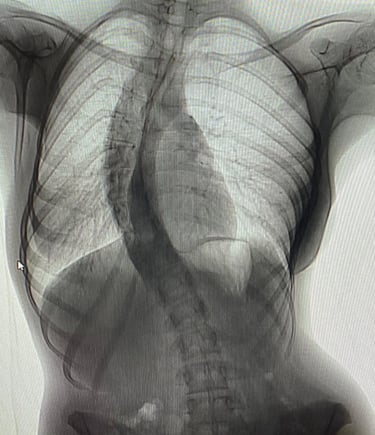

TEDAViLERiMiZ

Prof. Dr. Söyüncü çocukluk ve yetişkin döneminde karşılaşılan skolyoz, kifoz, bel ve boyun fıtıkları ve spinal kanal darlıkları, omurga enfeksiyonları, tümörleri, travmatik ve osteoporotik kırıkları gibi her türlü omurga rahatsızlıklarının tedavi ve cerrahileri ile diğer ortopedik rahatsızlıkların tedavileri ile ilgilenmektedir.